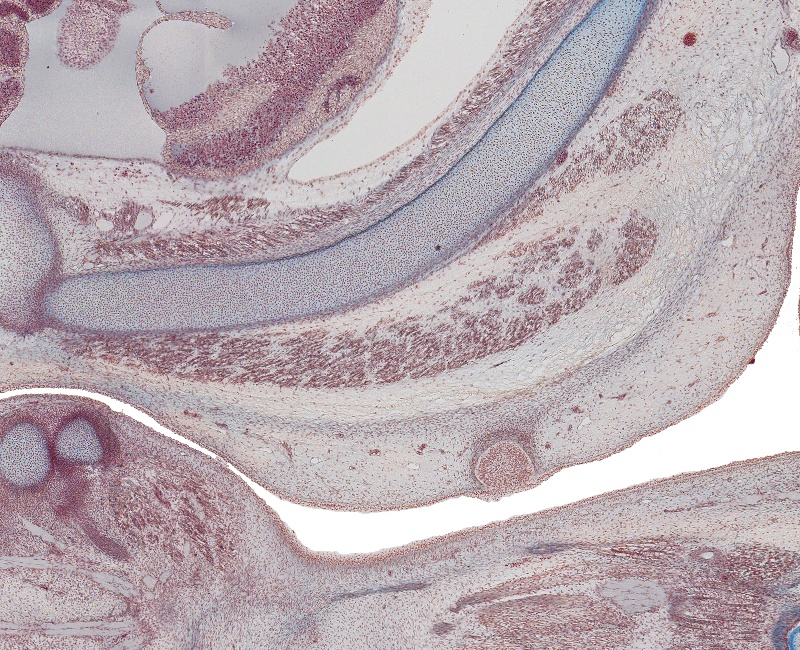

Tissue

–

Lt. Nipple and Costal Cartilage

Carnegie Embryo #9226

Location:

105-01-01